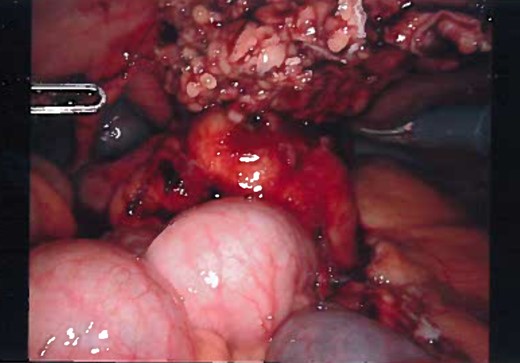

Patient was administered general anesthesia with placement of endotracheal tube. She was placed in lithotomy position (stirrups), both arms tucked at sides, strap secure across chest and a bair hugger (warmer) was placed around upper chest/head/neck area. Our patient was prepped with betadine for a vaginal/perineal prep and chloroprep was used on the abdomen. After sterile draping of the patient, and official time-out with all in agreeance, the Urologist evaluated the bladder with a cystoscopy using a 70° scope to survey for any persistent urachal abnormalities, and confirmed that no fistula/congenital abnormalities from inside bladder. General Surgeon scrubbed in and proceeded with insertion of veress needle and insufflated the abdominal cavity with CO2. Once the abdominal pressure reached 15 mmHg, General Surgeon used a 5 mm/0° laparoscope inside a 5 mm first-entry trocar and watched himself insert the trocar through each layer until passing through the peritoneum and into the abdominal cavity. Two 8 mm robotic Xi trocars were inserted, a 12 mm AirSeal Assistant port, and the 5 mm first entry port was replaced with a third robotic 8 mm cannula. Altogether 3–8 mm robotic ports, a 12 mm assistant port, and a 30° robotic scope was utilized during the case. Docking of the robot followed port placement with ‘renal right’ selected on the patient cart while the patient was placed in slight Trendelenburg. Da Vinci Xi instruments used were a fenestrated bipolar and a monopolar scissor to begin dissection. Initial survey of abdomen confirmed that there is an extension of a structure from the dome of the bladder to the posterior surface of the umbilicus (Fig. 4) and more suggestive of an infected urachal cyst. Further evaluations revealed that the cyst surrounding the umbilicus is inflamed and had multiple pus filled cavities. A complete resection of the cyst and the connecting structure was resected by Da Vinci Xi robotic system (Fig. 5). The bladder was filled with 300 ml of sterile normal saline mixed with methylene blue dye through the Foley catheter to determine any bladder otomies from the dissection. None were present. Urologist over sewed a thin area of the bladder with a 3-0 vicryl SH suture (Fig. 6). Complete resection of the cyst was performed successfully (Fig. 8). Slight irrigation was used to check for bleeding and the specimen was put in an endocatch bag to be retrieved when ports are ready for removal. A 19 Fr Blake drain was placed in the abdominal cavity and secured with a 2-0 nylon suture. Foley catheter is also indwelling.

Laparoscopic view of the urachal cyst, viewing the umbilical portion of the urachus.

Laparoscopic view of the urachus while dissection, view of the dome of the bladder and dissection of median umbilical ligament.